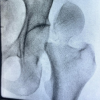

Over the course of 2 years, 80 patients presented with patella fractures at our center, out of which 12 patients had comminuted patella fractures. Informed consent was obtained from 12 patients and who were included in the study. Out of 12 patients, One was female and 11 were male. The average age was found to be 42 years. The average time of follow-up was 1.2 years. Out of 12 patients, all 12 (100%) achieved union. One patient (8%) had anterior knee pain and difficulty while kneeling due to implant impingement. No elective implant removal was done. One patient (25/Male) had suffered a transverse patella fracture, which was fixed using standard tension band wiring, following which he again suffered a fall to the same knee 2 weeks postoperatively, which had resulted in failure of tension band wiring and comminution of the fracture fragments (Fig. 5a and b). The tension band wiring was removed, the fracture was reduced and fixed using a star-shaped patella plate, which had gone onto the united well (Fig. 5g-l), and achieved knee flexion of 130° without any extensor lag at 1-year follow-up (Fig. 6).

During follow-up, all the patients had full recovery of the extensor mechanism. The mean flexion achieved was 123° (110–130°), six patients achieved knee flexion of 120°, whereas five patients achieved 130° of knee flexion (Fig. 7 and 8). Almost all patients were able to sit cross-legged except one patient with pre-existing medial compartment osteoarthritis.